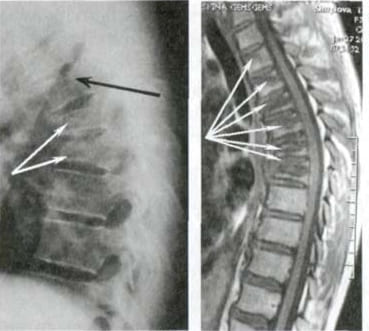

Mire esta radiografía. Es la columna de una persona de 44 años, pero parece la de un anciano. Antes, este tipo de daño aparecía después de los 60 años y, hoy, es muy común en personas de poco más de 40. Estos cambios progresan con la edad, y ignorarlos amenaza con una pérdida completa de movilidad.

Columna de un paciente de 44 años: todo comenzó con un dolor simple, pero en una semana apareció la hernia, y en dos semanas — desplazamiento de las vértebras, compresión de nervios y silla de ruedas.